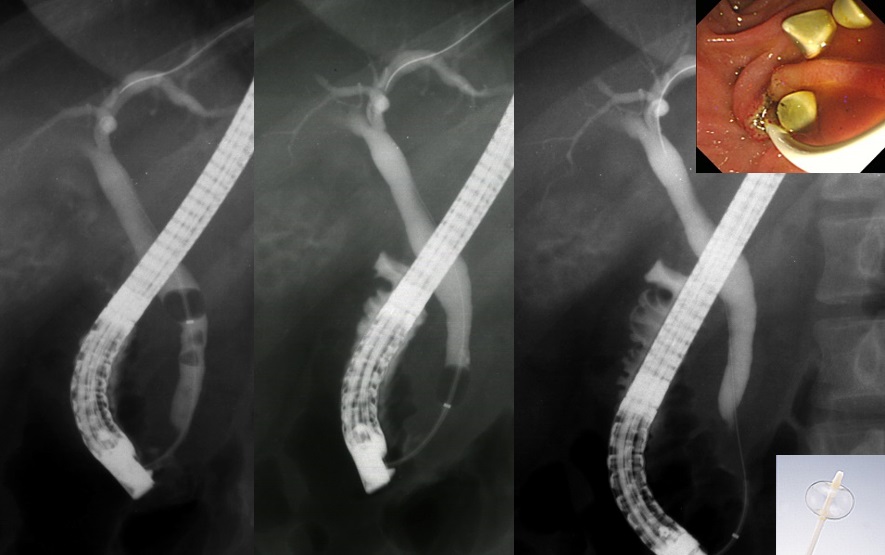

『内視鏡を用いた胆管結石除去術』